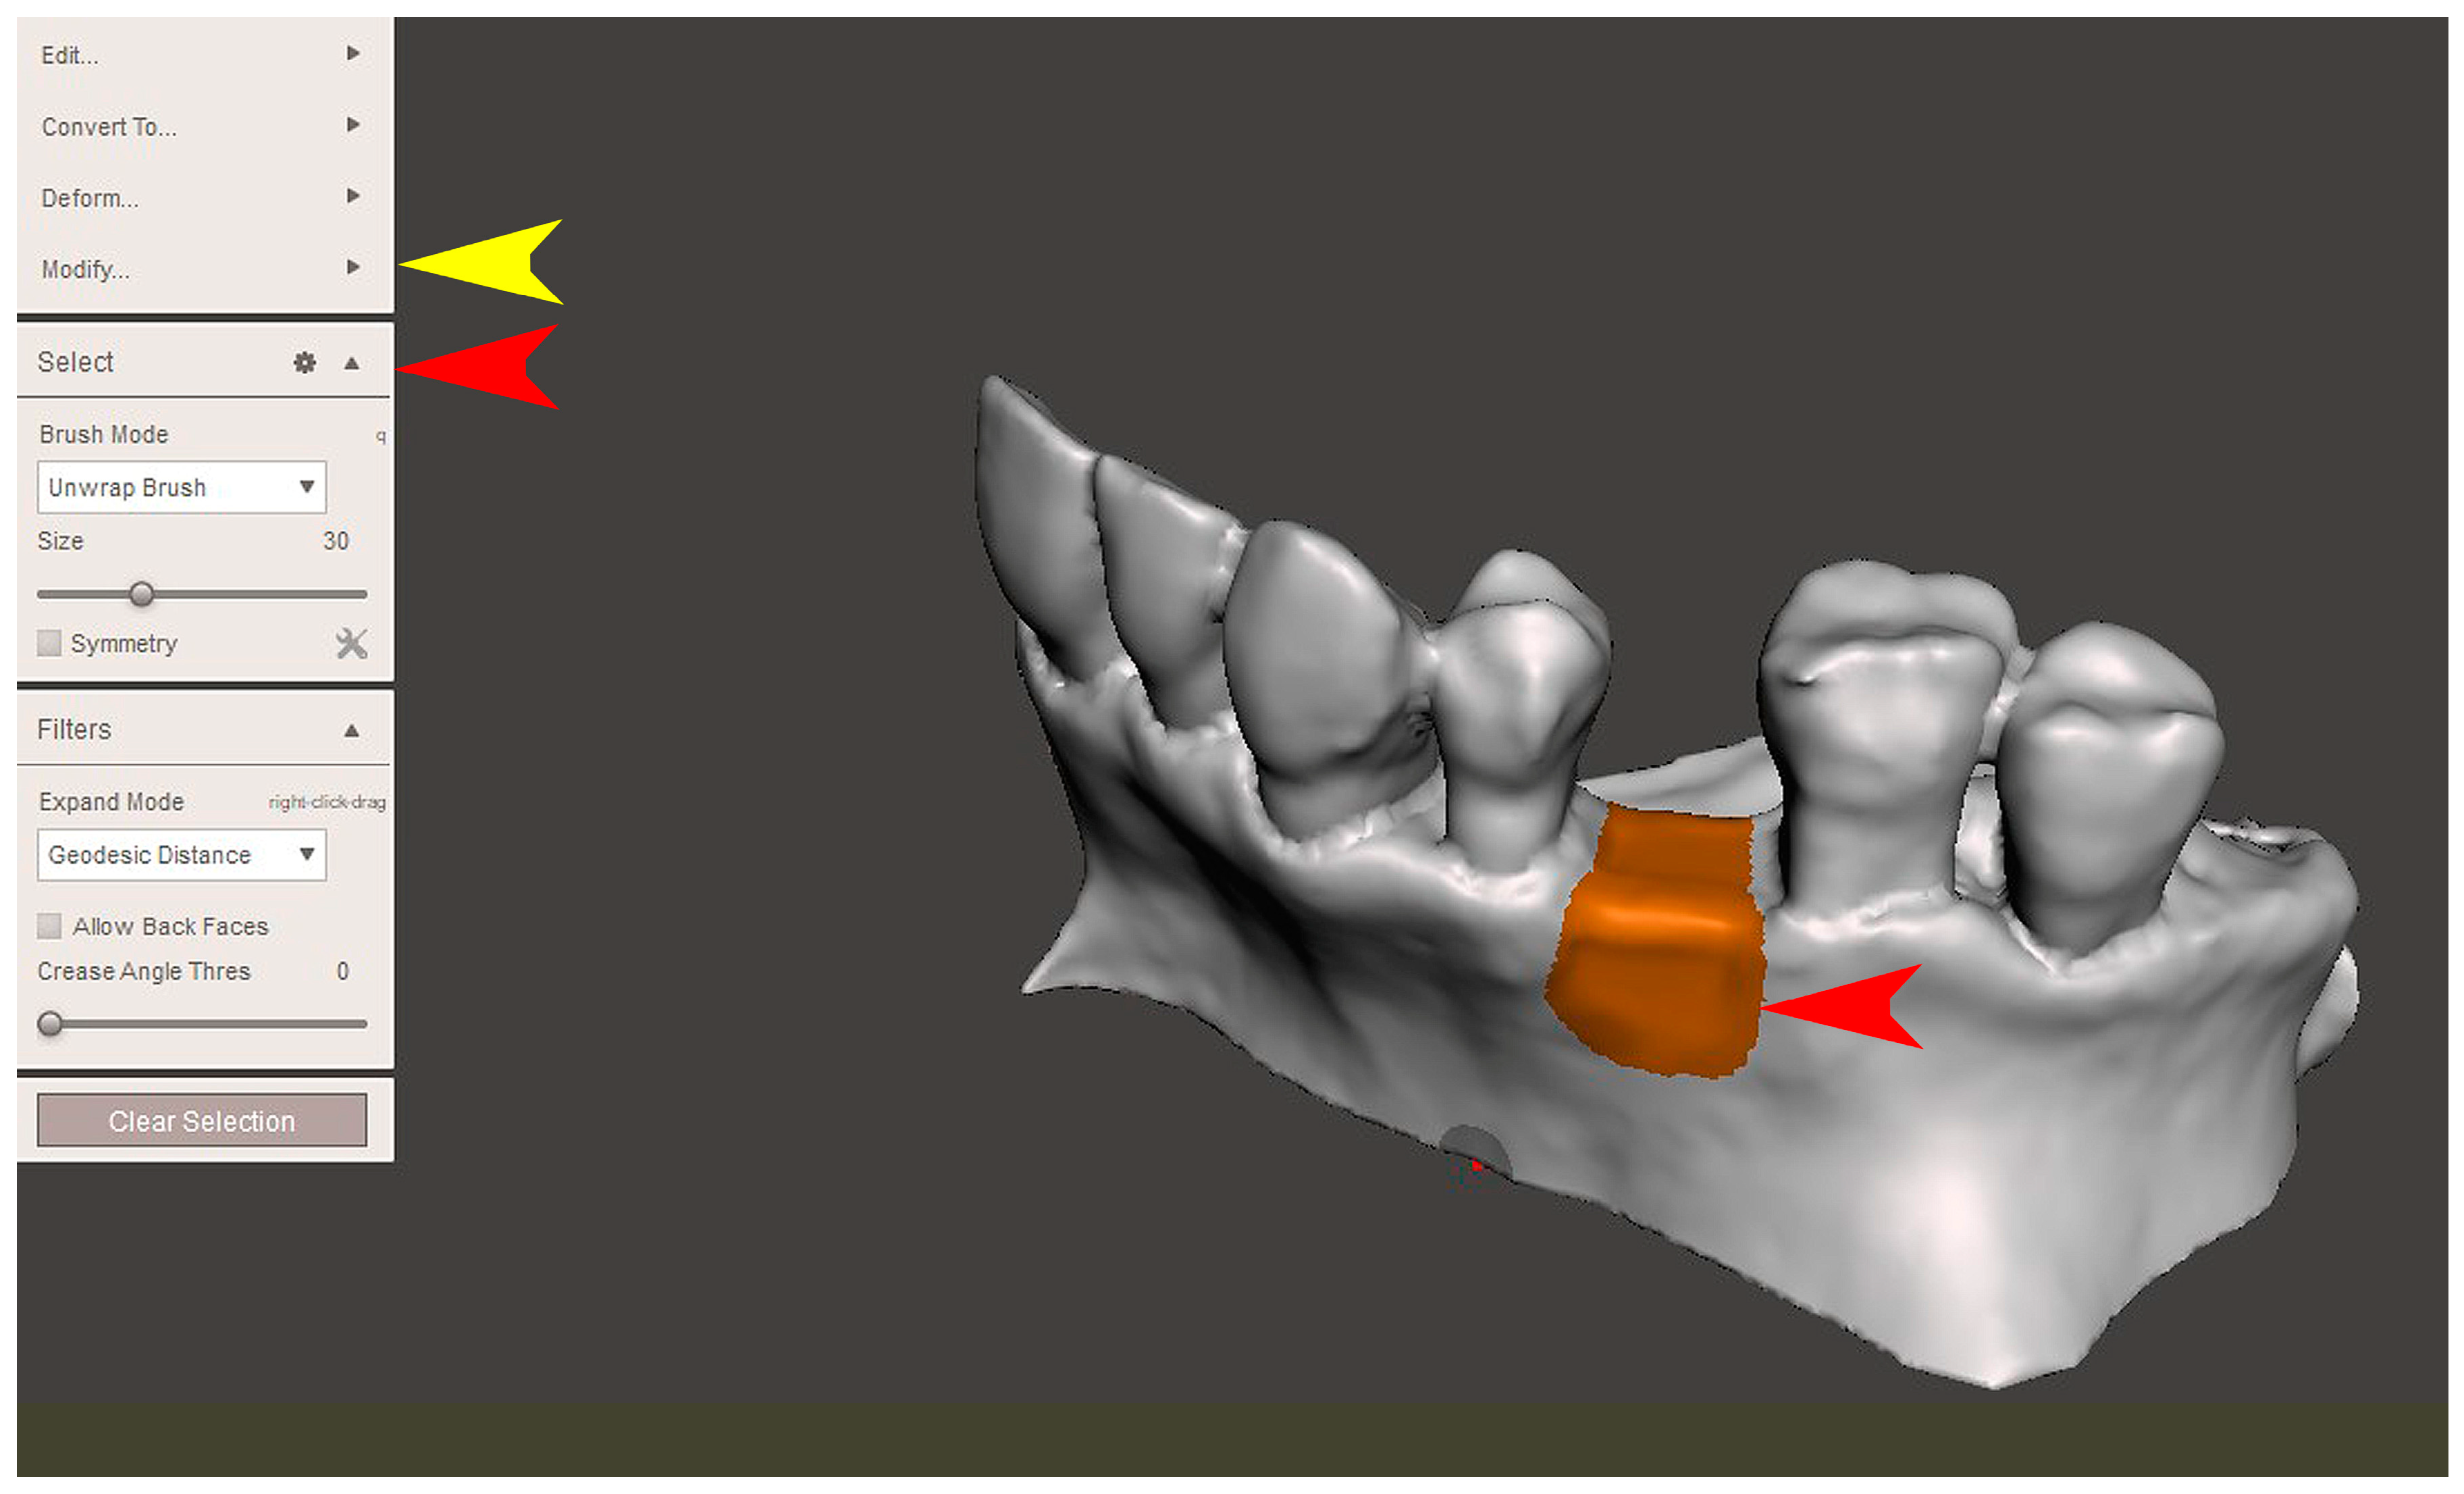

2.2. GBR Simulation and Mesh Design